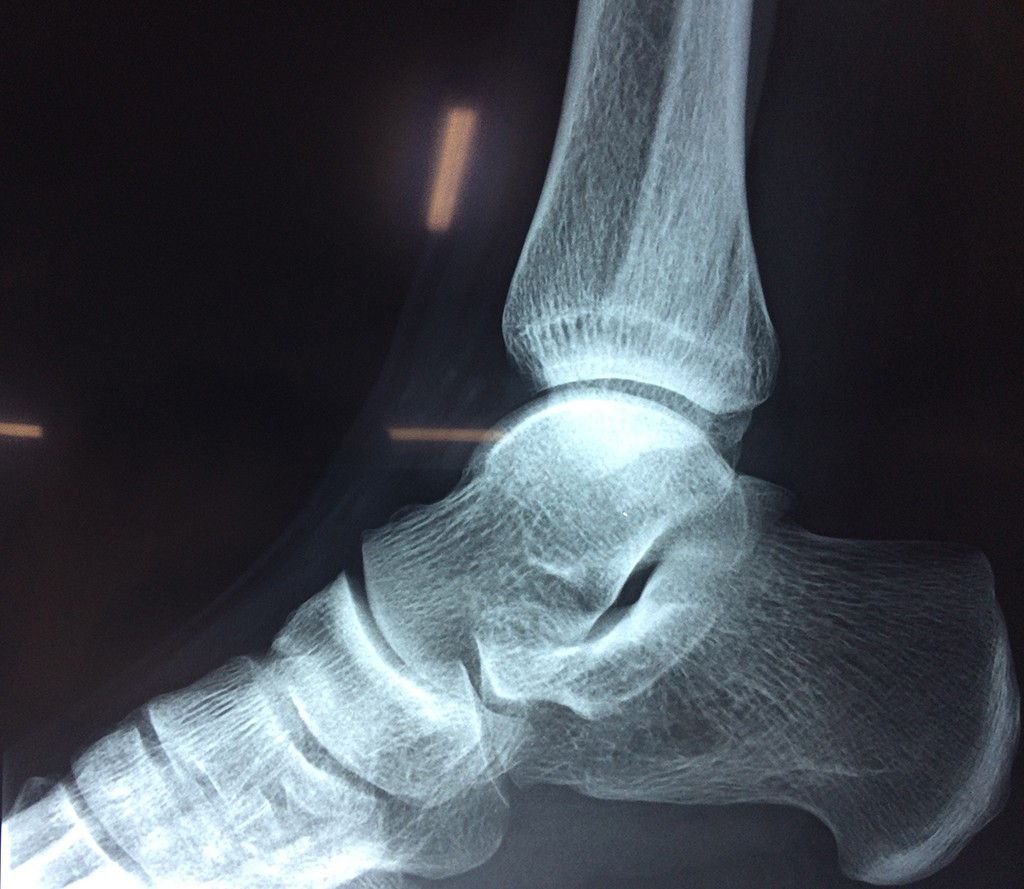

Una fractura de tobillo es la rotura de uno o más de los huesos del tobillo. Estas fracturas pueden ser:

- Parciales (el hueso está sólo parcialmente fisurado, no del todo).

- Completas (el hueso está perforado y está en 2 partes).

- Producirse en uno o ambos lados del tobillo.

- La fractura se extiende hasta la articulación del tobillo (fractura intra-articular).